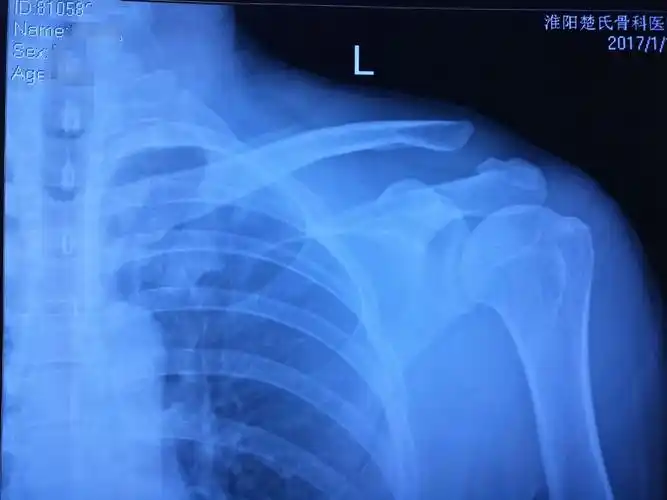

请问左肩锁关节脱位需要手术吗

肩锁关节脱位rockwoodⅥ型

肩锁关节脱位

我爸摔伤,可能是肩锁关节脱位,请问医生治疗方法和有什么影响不,谢谢